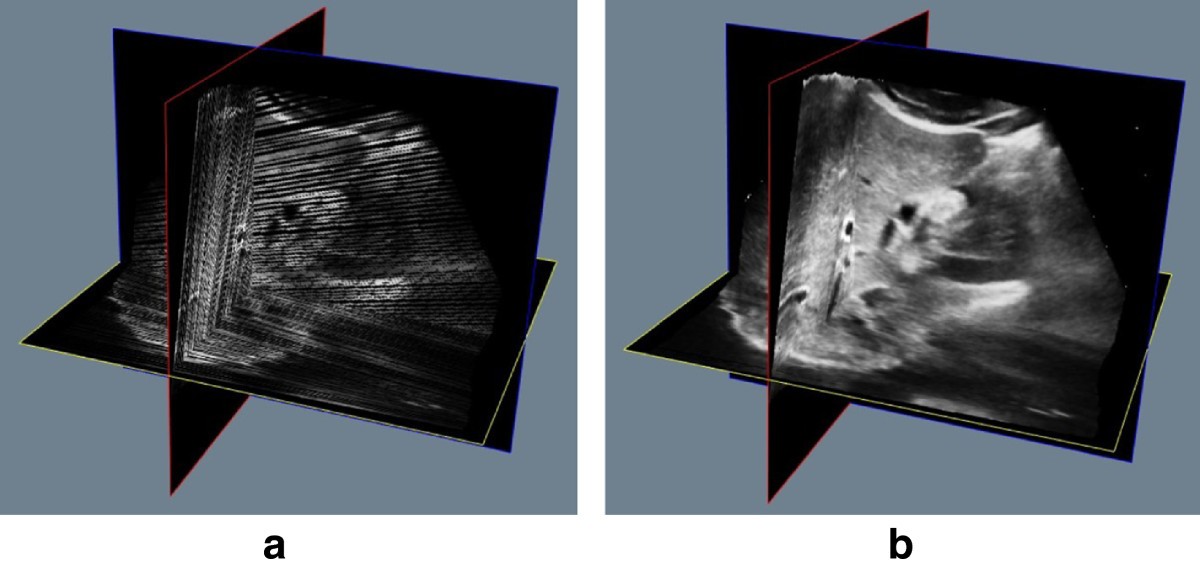

Reconstruction of freehand 3D ultrasound based on kernel regression Freehand Three-Dimensional Ultrasound Calibration The role of calibration is to find the mathematical. Chapter 3 freehand 3d ultrasound calibration: The role of calibration is. Freehand Three-Dimensional Ultrasound Calibration.